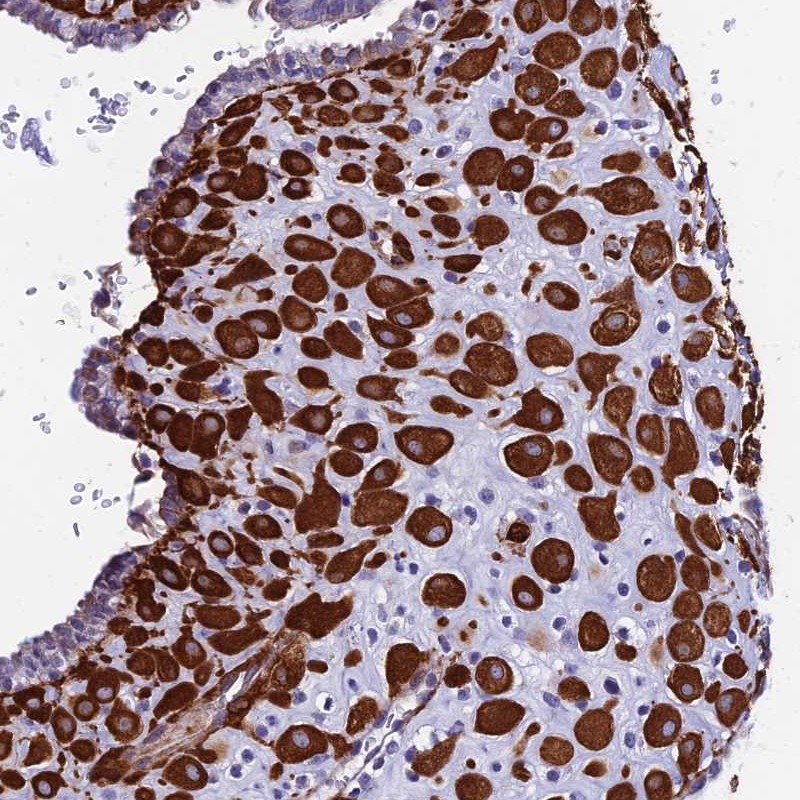

Immunohistochemical staining of human placenta shows strong cytoplasmic positivity in decidual cells.